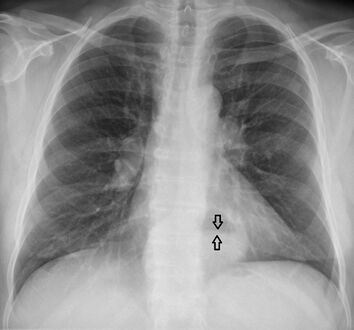

تنظير الجهاز الهضمي العلوي في وضع الانثناء للخلف يظهر الفتق الحجابي من النوع الأول.